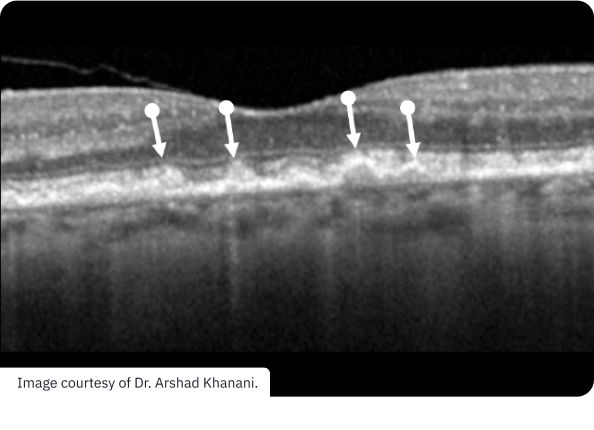

Drusen are a hallmark of early AMD, which can be observed by direct examination of color fundus photography (CFP) or optical coherence tomography (OCT).1,2,5,6 Drusen come in various sizes. The larger the drusen, the greater the chance of progression to an advanced form of AMD such as GA.1,2

Early AMD with drusen (white arrows). Pigmentary abnormalities are absent. Drusen are found between the RPE basement membrane and Bruch’s membrane.3